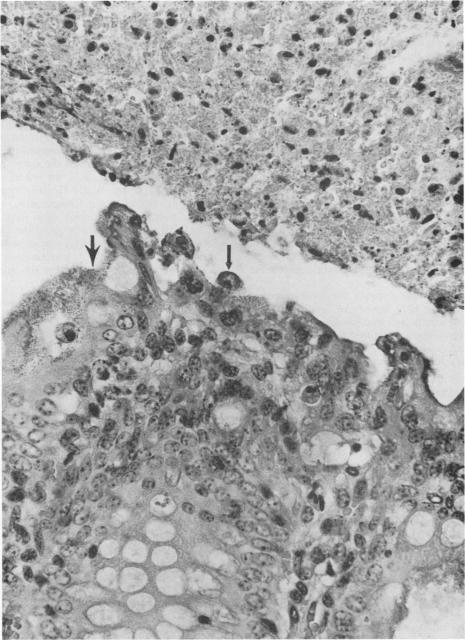

Escherichia coli, rotaviruses, and Cryptosporidium parvum are discussed in this review as they relate to enteric disease in calves, lambs, and pigs. These microorganisms are frequently incriminated as causative agents in diarrheas among neonatal food animals, and in some cases different strains or serotypes of the same organism cause diarrhea in humans. E. coli causes diarrhea by mechanisms that include production of heat-labile or heat-stable enterotoxins and synthesis of potent cytotoxins, and some strains cause diarrhea by yet undetermined mechanisms. Rotaviruses and C. parvum induce various degrees of villous atrophy. Rotaviruses infect and replicate within the cytoplasm of enterocytes, whereas C. parvum resides in an intracellular, extracytoplasmic location. E. coli, rotavirus, and C. parvum infections are of concern to producers, veterinarians, and public health officials. These agents are a major cause of economic loss to the producer because of costs associated with therapy, reduced performance, and high morbidity and mortality rates. Moreover, diarrheic animals may harbor, incubate, and act as a source to healthy animals and humans of some of these agents.